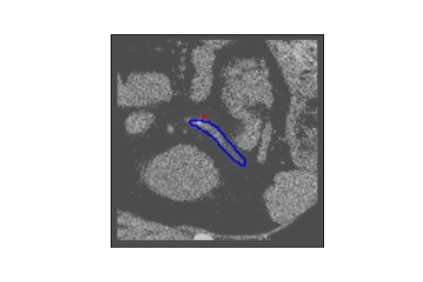

The human annotations are imperfect, especially when produced by junior practitioners. Multi-expert consensus is usually regarded as golden standard, while this annotation protocol is too expensive to implement in many real-world projects. In this study, we propose a method to refine human annotation, named Neural Annotation Refinement (NeAR). It is based on a learnable implicit function, which decodes a latent vector into represented shape. By integrating the appearance as an input of implicit functions, the appearance-aware NeAR fixes the annotation artefacts. Our method is demonstrated on the application of adrenal gland analysis. We first show that the NeAR can repair distorted golden standards on a public adrenal gland segmentation dataset. Besides, we develop a new Adrenal gLand ANalysis (ALAN) dataset with the proposed NeAR, where each case consists of a 3D shape of adrenal gland and its diagnosis label (normal vs. abnormal) assigned by experts. We show that models trained on the shapes repaired by the NeAR can diagnose adrenal glands better than the original ones. The ALAN dataset will be open-source, with 1,594 shapes for adrenal gland diagnosis, which serves as a new benchmark for medical shape analysis. Code and dataset are available at https://github.com/M3DV/NeAR.